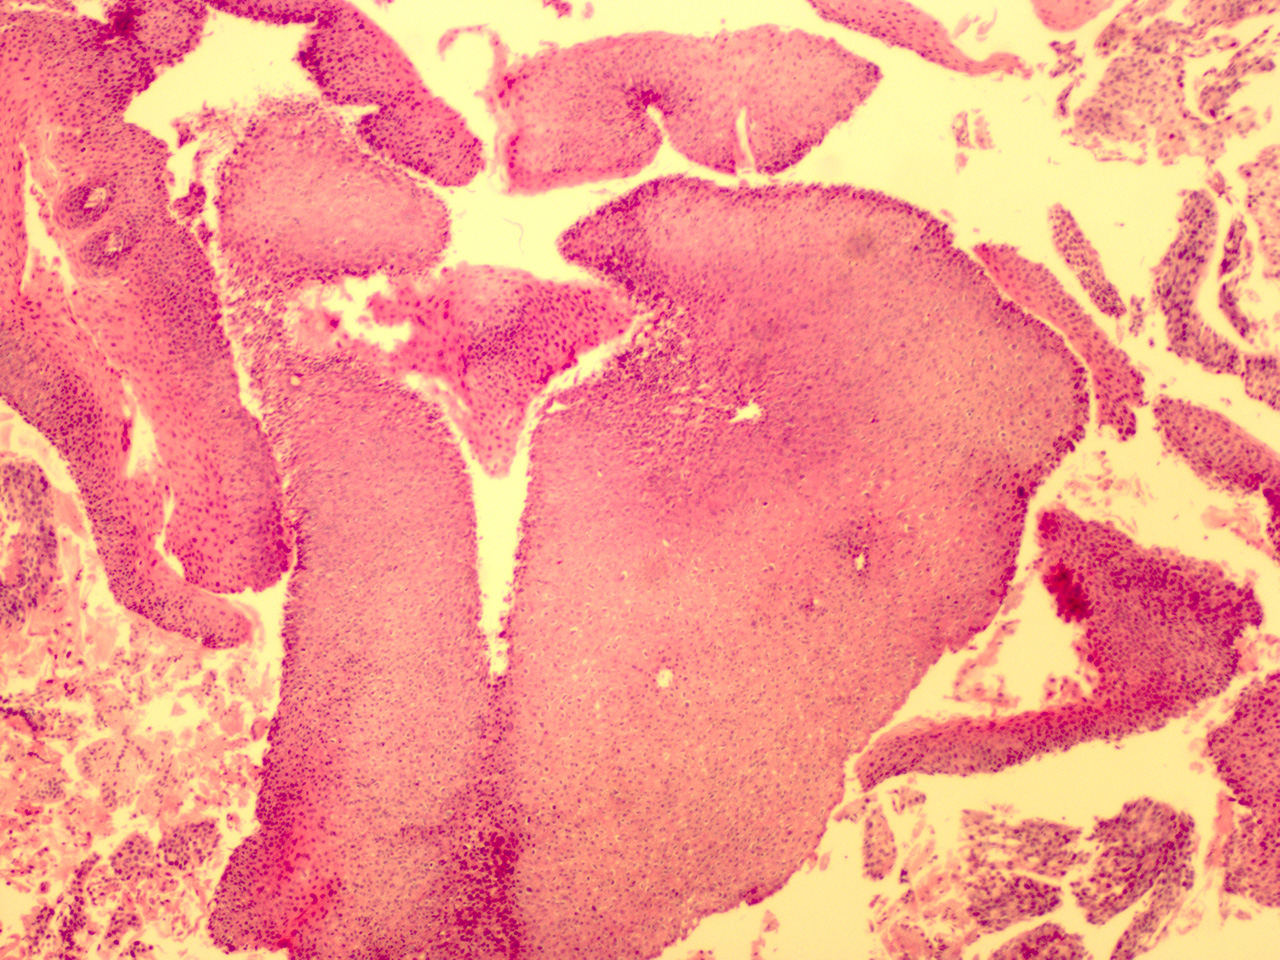

Case 3

Soft Bx CIN 2-3 10x - Low Power

![]() Case 3

Soft Bx CIN 3

10x - Low Power |